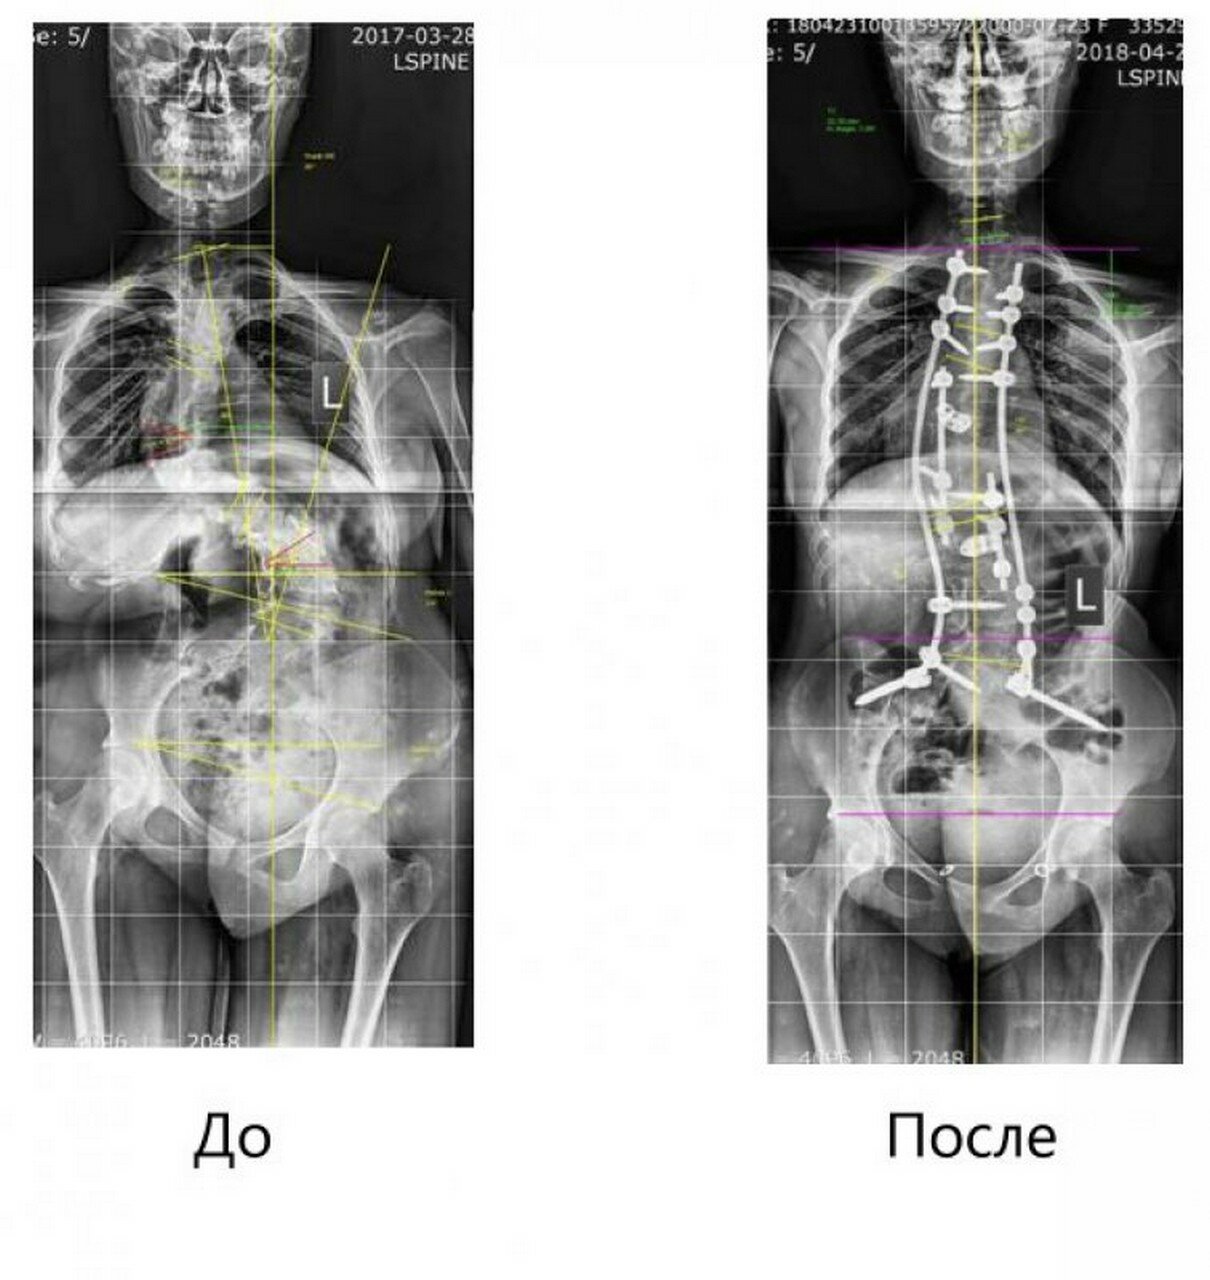

Нейрохирурги университетской клиники ПИМУ успешно прооперировали 17-летнюю пациентку с врожденным сколиозом, деформацией позвоночника, перекосом таза и нарушением баланса тела. Об этом сообщает пресс-служба Приволжского медуниверситета.

«При планировании хирургического вмешательства была воссоздана 3D-модель позвоночника пациентки. После операции, которая длилась 11 часов, были до 60% скорректированы фронтальные дуги деформации, восстановлено нормальное положение таза, сагиттальный и фронтальный баланс позвоночника»,- сообщили в медицинском вузе.